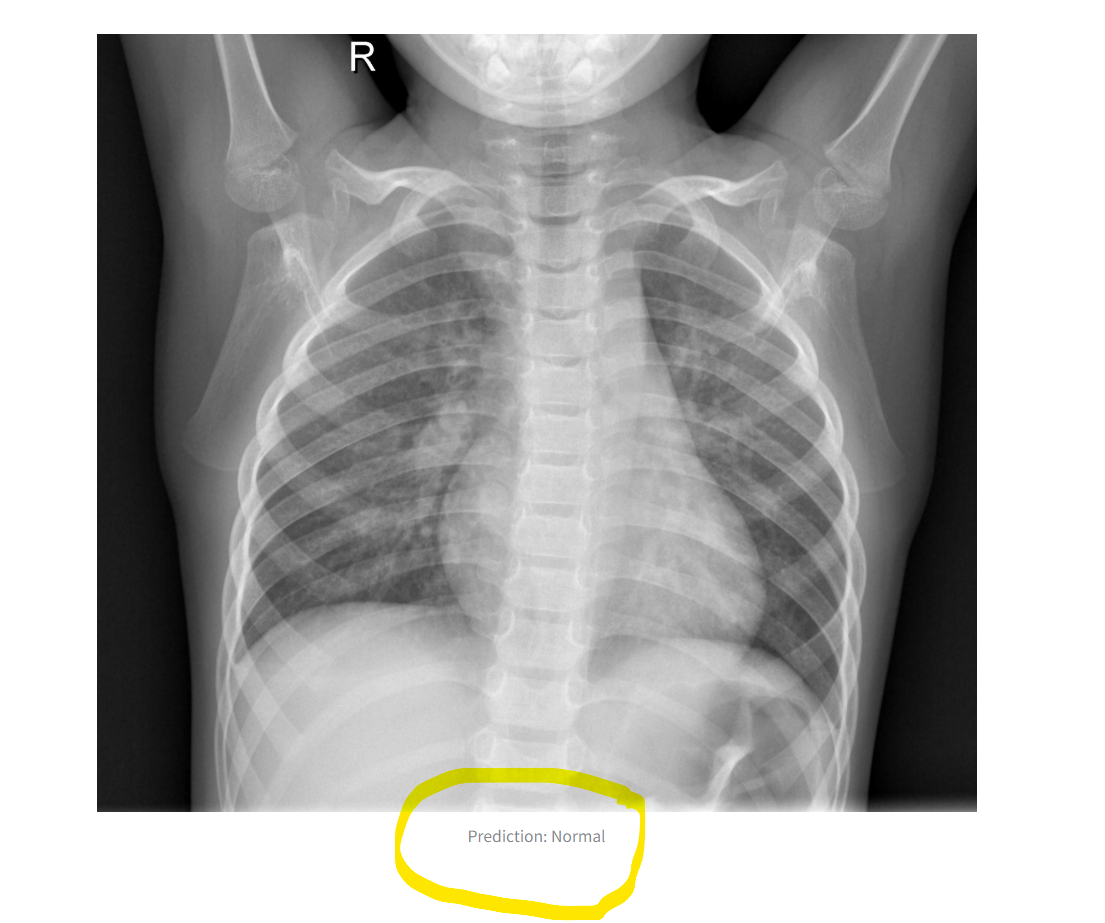

The application demonstrates reliable performance on test images. It accurately distinguishes between "Normal" and "Pneumonia" cases when provided with valid X-ray images. Results are displayed directly in the Streamlit interface, making it accessible for non-technical users. See the image below:

The output image and label

The original image is displayed alongside the prediction result.

The model determines the class label (Normal or Pneumonia) based on the highest probability.